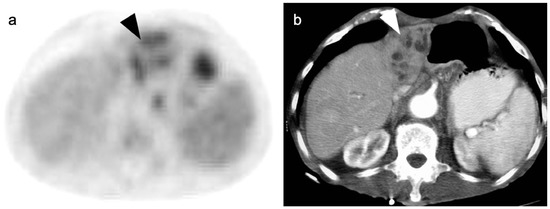

4. Hepatocellular Carcinoma